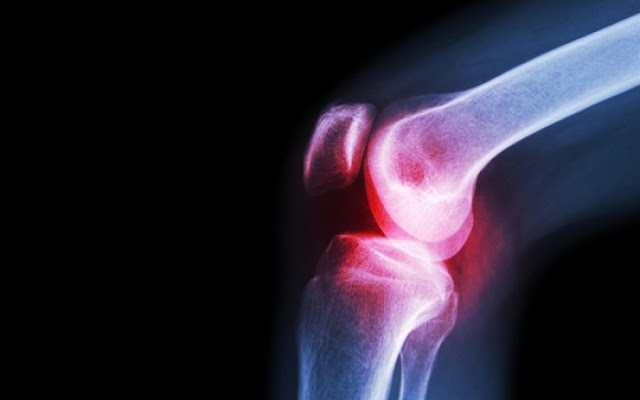

Όταν υπάρχει φλεγμονή στις αρθρώσεις , με αποτέλεσμα αυτές να σκληραίνουν και να πρήζονται, ο πόνος μπορεί να γίνει πραγματικά ανυπόφο...

Όταν υπάρχει φλεγμονή στις αρθρώσεις, με αποτέλεσμα αυτές να σκληραίνουν και να πρήζονται, ο πόνος μπορεί να γίνει πραγματικά ανυπόφορος.

Υπολογίζεται ότι 1 στους 5 ενήλικες αντιμετωπίζει κάποια από τις περίπου 100 ιατρικές παθήσεις που επηρεάζουν το μυοσκελετικό σύστημα και ειδικά τις αρθρώσεις, όπου συναντώνται δύο ή περισσότερα οστά.

Και ενώ ο πόνος στις αρθρώσεις δεν εξαφανίζεται για πάντα, προσαρμόζοντας τη διατροφή σας, βοηθάτε το σώμα σας να αντιμετωπίσει καλύτερα τις αρθρίτιδες.